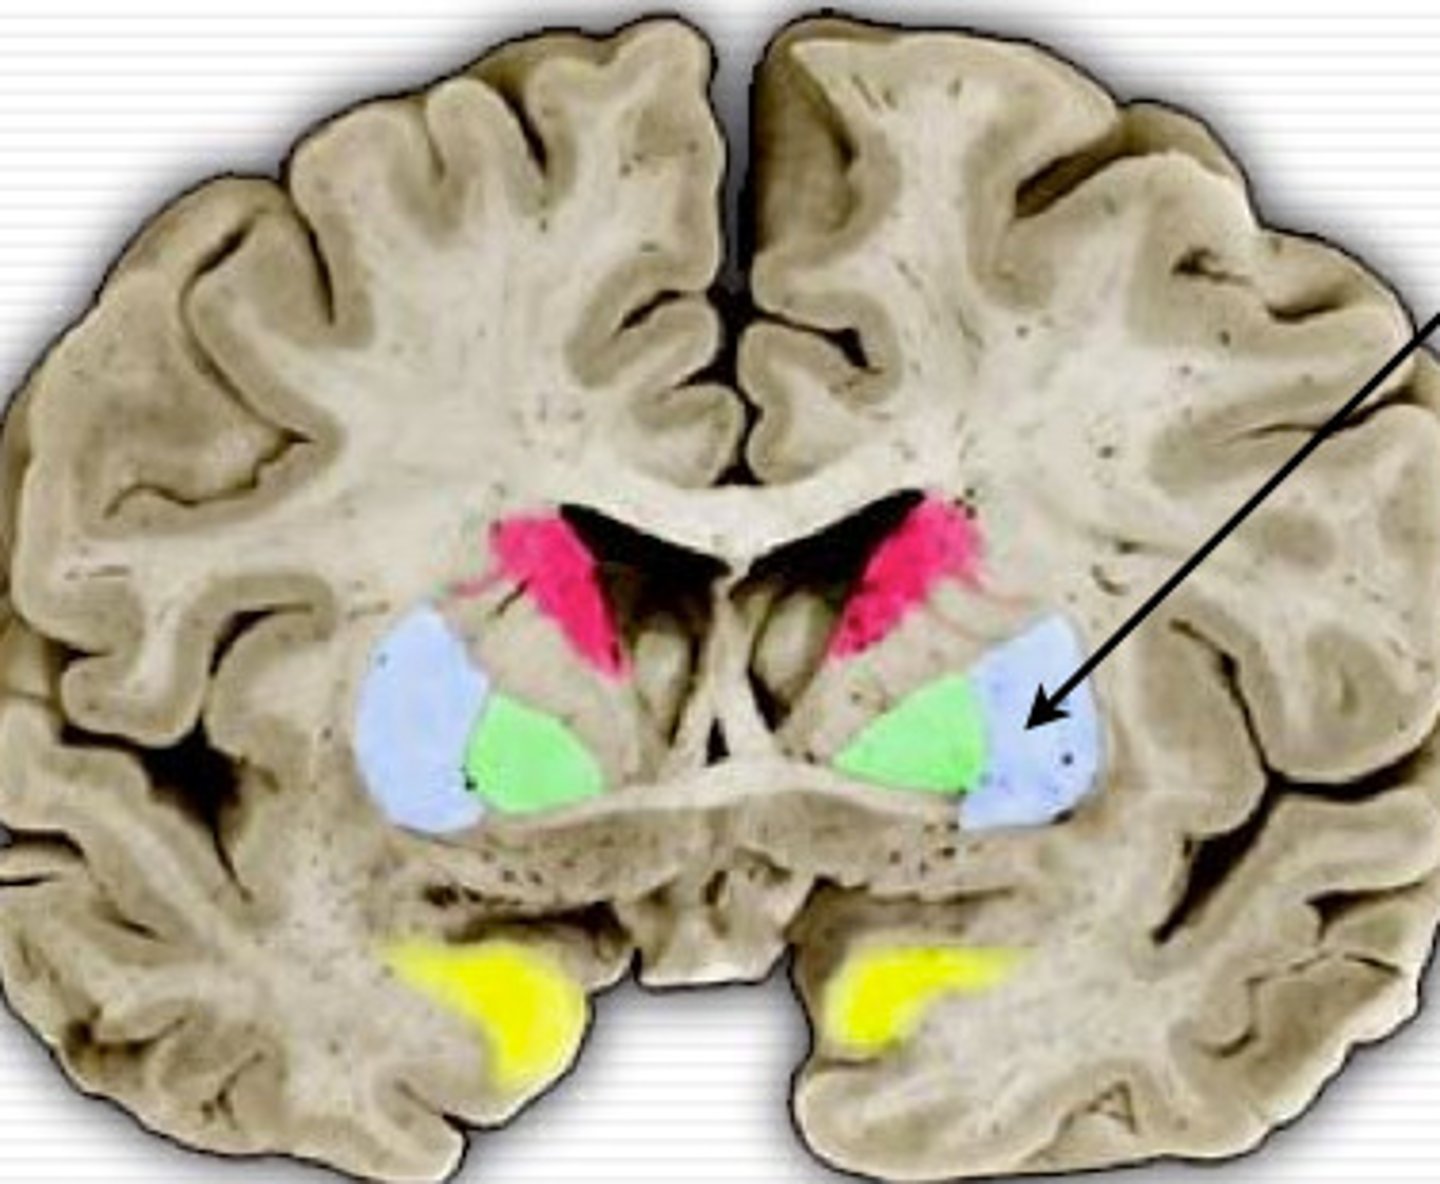

Basal Ganglia

a group of nuclei located at the base of the cerebral cortex made of 7 functional parts involved in movement control

what nuclei make up the basal ganglia

caudate

putamen

globus pallidus (interal and external)

sibstantia nigra (paras compacta and paras reticulata)

subthalamic nucleus

Striatum

the combined structure of the caudate + putamen and the main input area of the basal ganglia

Lentiform (lenticular) nucleus

the combined structure of the globus pallidus + putamen, cone-shaped

Caudate nucleus

a C-shaped input nucleus divided into head, body, and tail, main inphut of the basal ganglia

lateral "shell" oof basal ganglia with cellular bridges to caudate nucleus

Globus pallidus (segments, location and roles)

2segments

GPi (internal) → medial

GPe (external) → lateral

Medial to putamen

One of the major outputs

Has inhibitory connections with thalamus